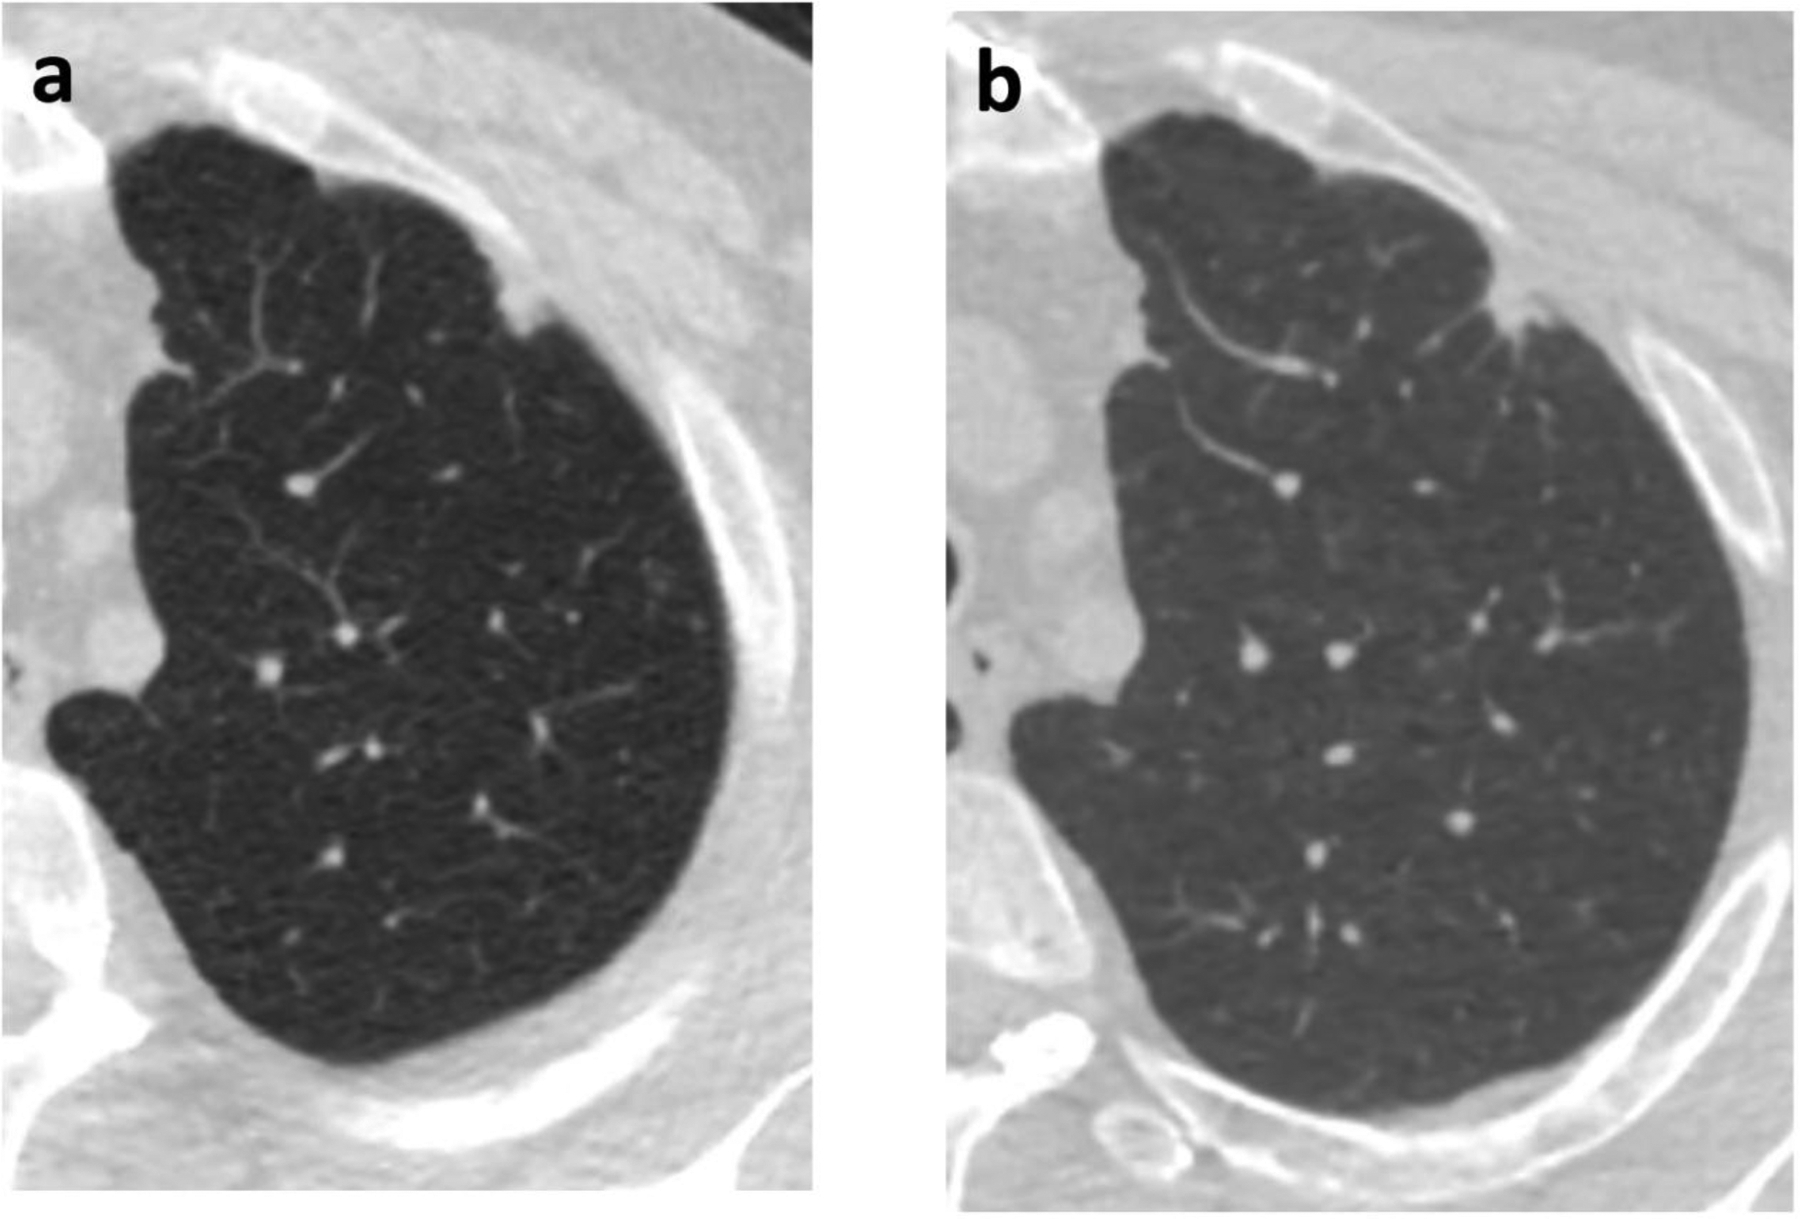

Overall, 30/44 (68%) of malignant nodules and 36/109 (33%) of benign nodules grew by NELSON algorithm criteria (p<0.001). By density, 10/12 (83%) of malignant ground glass nodules and 8/15 (53%) of benign ground glass nodules grew; 7/8 (88%) of malignant part-solid nodules and 2/3 (67%) of benign part-solid nodules grew; and 13/24 (54%) of malignant solid nodules and 26/91 (29%) of benign solid nodules grew. An example of a solid malignant nodule that did not grow is shown in Figure 1.

Figure 1.

60-year-old man with a left upper lobe solid subpleural nodule. (a) Initial chest CT, at which time the nodule measured 11 mm in diameter with volume of 0.581 ml. (b) Follow-up CT after 364 days, when the volume was 0.531 ml. Subsequent wedge resection demonstrated adenocarcinoma